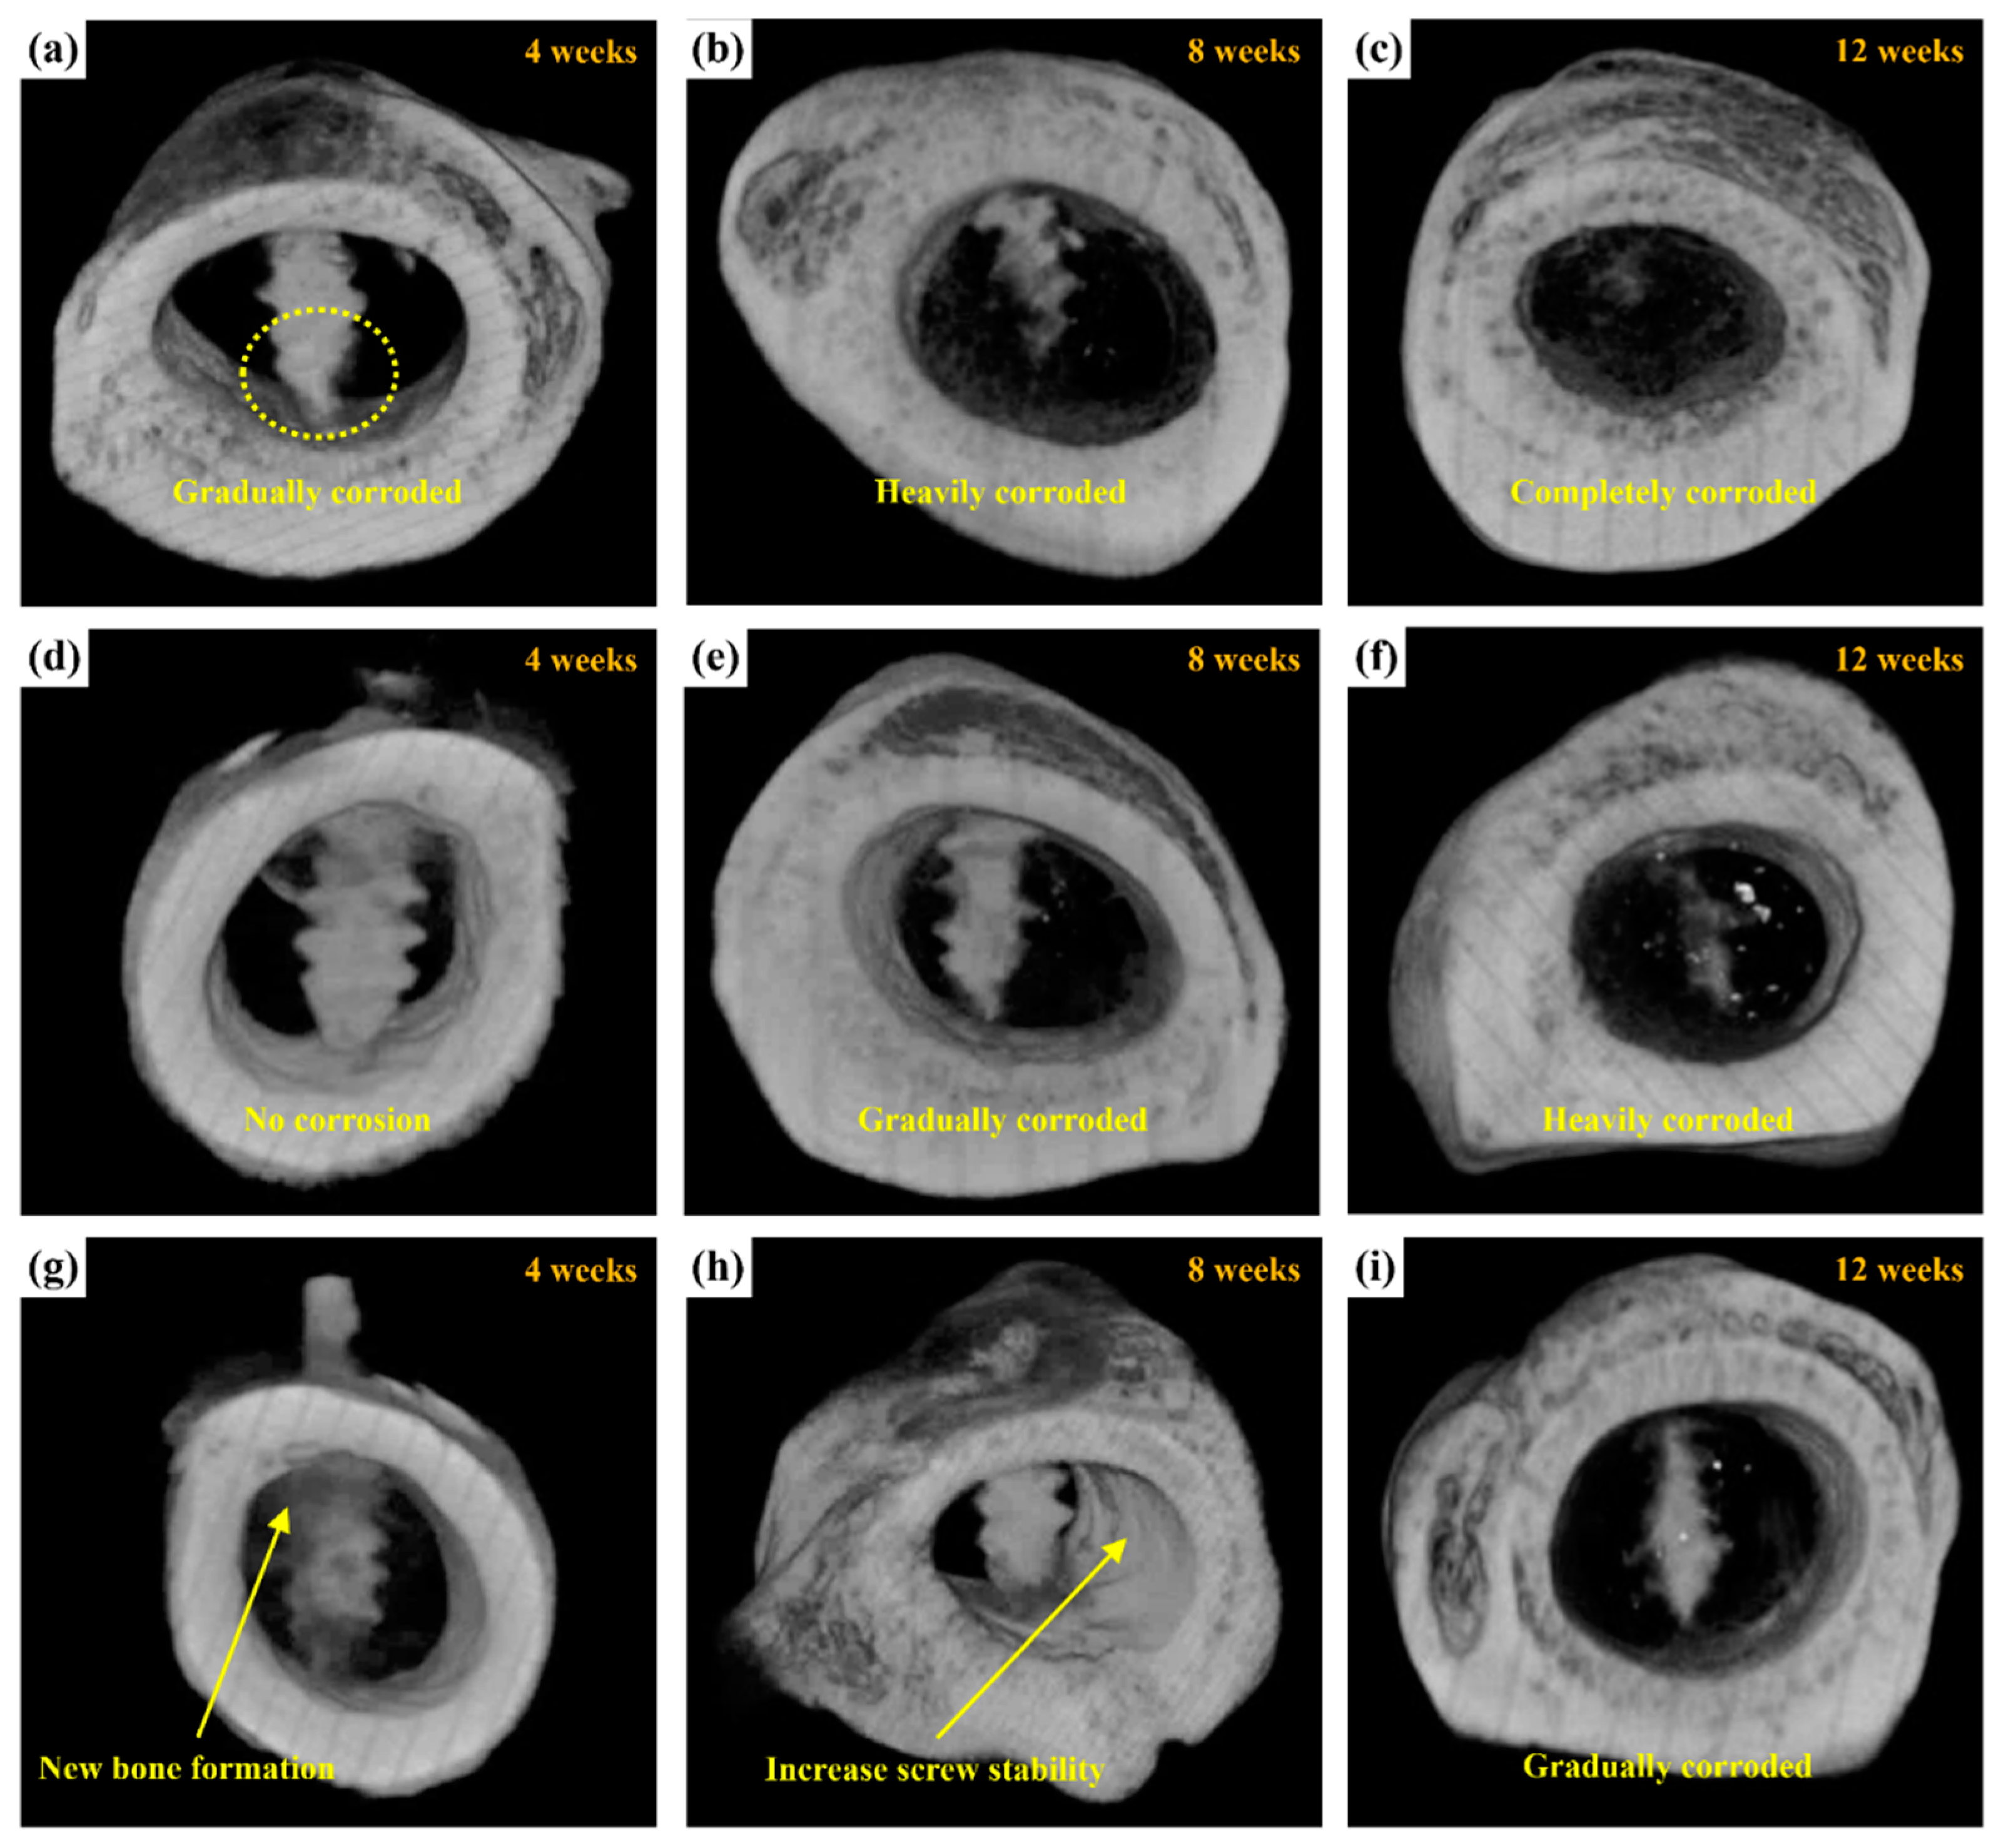

2.3.3. Micro-CT Scanning

Figure 14 shows micro-CT images of the untreated, MAO-treated, and MAOCa-treated ZK60 bone screws 12 weeks after implantation, which were used to further evaluate the bone growth and growth properties of the implanted screws. Compared with X-ray detection (Figure 13), the bone screw implantation method in this section involved implanting the bone screws from each process into rabbit bone separately. After 4 weeks of implantation, the lower part of the untreated ZK60 bone screw began to corrode, while the others exhibited no corrosion phenomenon, as shown in Figure 14a,d,g. The untreated ZK60 bone screw was completely corroded after 12 weeks of implantation (Figure 14c). Similarly, the MAO-treated ZK60 bone screw also suffered severe corrosion 12 weeks after implantation (Figure 14f). The most interesting finding in this study was that the μCT images revealed that the bone grew around the MAOCa-treated ZK60 bone screws, and the osteotomy sites healed well (Figure 14g). This indicated that the sample exhibited superior osteoconduction properties. Simultaneously, we identified some newly formed bone tissues that dominated the repaired space. As the implantation time increased, the bony tissues gradually transformed into bone and bone screws without active signs of degradation throughout the experimental period, as shown in Figure 14h. Most of the newly formed bones were also in close contact with the MAOCa-treated ZK60 bone screws and were distributed evenly throughout the repaired space. The addition of bone grafting materials could create more space and mediate osteogenesis [50,54]. In this study, MAOCa treatment induced more bone tissue growth.

Figure 14.

μCT reconstructed images showing the degradation processes of ZK60 bone screw after implantation for 4, 8, and 12 weeks: (a–c) untreated, (d–f) MAO-treated, and (g–i) MAOCa-treated screw.